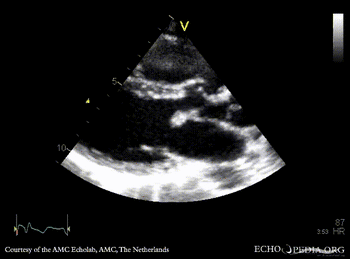

| Courtesy of: AMC Echolab, AMC, The Netherlands | |

| PSAX: Color Doppler, ASD type I | A4CH: Color Doppler ASD type I |